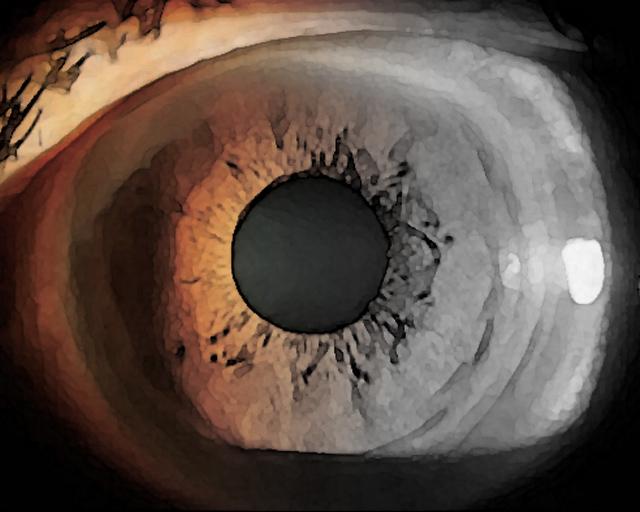

68歳の女性。5か月前からしばしば眼痛、虹視および軽度の頭痛を自覚しており、精査を希望して来院した。視力は右0.3(1.0×+2.5D)、左0.2(1.0×+3.0D)。眼圧は右19mmHg、左24mmHg。左眼の細隙灯顕微鏡写真を別に示す。